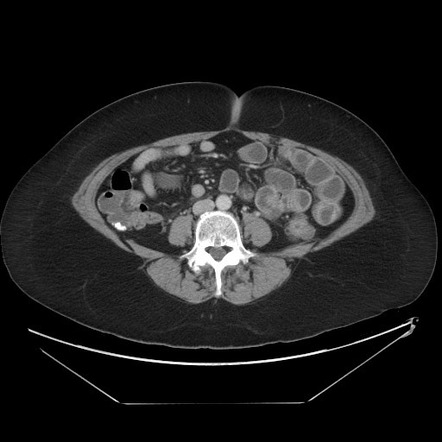

Компьютерная томография при подозрении на гастриному проводится с внутривенным контрастированием в артериальную и венозную фазы, с применением тонкосрезового протокола в области поджелудочной железы, двенадцатиперстной кишки, печени и лимфатических коллекторов. Цель обследования — выявление гиперваскулярной нейроэндокринной опухоли, продуцирующей гастрин, которая может вызывать клинический синдром Золлингера—Эллисона, проявляющийся рецидивирующими язвами желудка и гиперсекрецией соляной кислоты.

КТ выявляет следующие признаки гастриномы:

Гиперваскулярное образование в области головки или тела поджелудочной железы, размером от 3 до 20 мм, с плотностью более +120 HU в артериальную фазу и частичным выравниванием контрастирования в венозную фазу.

Очаговое утолщение стенки нисходящей части двенадцатиперстной кишки с выраженным накоплением контраста, соответствующее интрамуральной гастриноме.

Умеренное или выраженное утолщение складок слизистой желудка, особенно в теле и дне, за счёт гиперплазии обкладочных клеток, вторичной к избытку гастрина.

Расширение просвета желудка и двенадцатиперстной кишки на фоне гиперсекреции желудочного сока.

Увеличенные парапанкреатические и брыжеечные лимфоузлы до 15 мм с повышенным артериальным кровотоком.

Гиперваскулярные метастатические очаги в печени, диаметром от 5 мм, с ярким артериальным контрастированием и последующим выравниванием в венозную фазу.